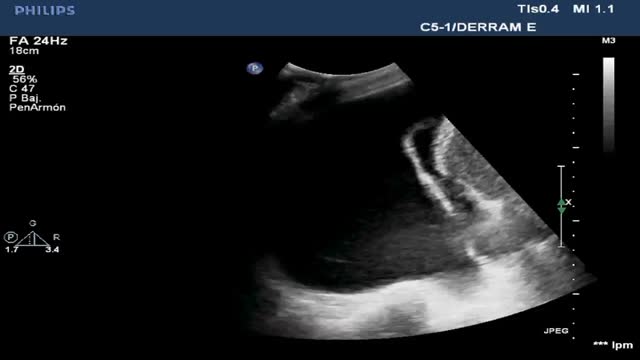

Alveolar consolidation or lung hepatization patternLung hepatization is described as a liver-like appearance of the consolidated lung seen at ultrasound exploration. This type of image is easier to visualize in supradiaphragmatic consolidations (Suppl. Fig. 6).

Pleural effusion (PE)Ultrasound assesses the volume (detecting millimetric magnitudes) and the characteristics of PE, guiding the site of puncture for evacuation of the effusion when needed. For this purpose, we ideally use a low-frequency convex probe (2.5-5 Hz), which sacrifices resolution in favor of greater ultrasound wave penetration capacity, reaching more in depth and visualizing the diaphragm and liver or spleen, and their relation to the lung parenchyma.

With the patient in the supine position, we place the probe on the mid-axillary line and locate the fundamental reference of the study: the diaphragm. All anechoic images above the diaphragm correspond to the chest cavity (pleural fluid). In contrast, such images located below the diaphragm correspond to the abdominal cavity (ascitic fluid)(Video 10).

Ultrasound signs related to pleural effusionPleural effusion is a genuine image, not an artifact. It is classically defined as an anechogenic component. The appearance of PE in critical patients is not always as described, however, since there may be coexisting hemothorax, complicated effusion and empyema, which are characterized by different degrees of echogenicity.

In terms of ultrasound exploration, PE is defined by the following signs:

Jellyfish sign: In the presence of a significant amount of intrapleural fluid, the underlying lung collapses, and the parenchyma exhibits a static air bronchogram. The atelectatic lung is contained within the PE and in the lower zone appears floating freely within the fluid, generating the characteristic movement of the jellyfish sign (Video 12).